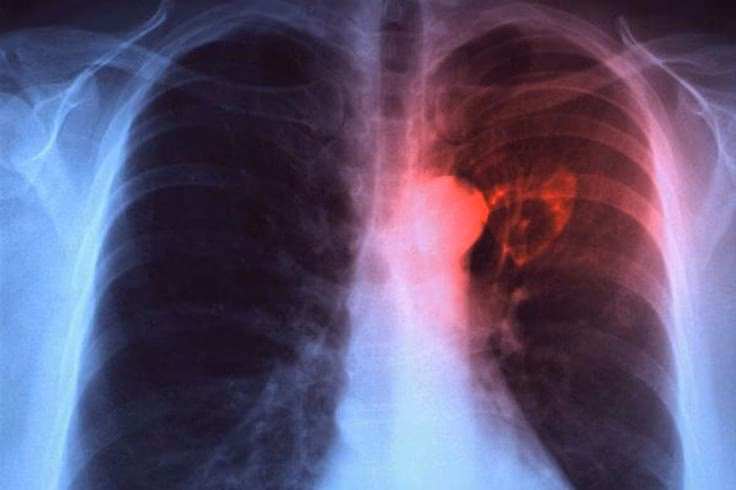

Der findes ingen specifik test, som definitivt kan påvise costochondritis. Diagnosen stilles primært klinisk. Lægen vil foretage en fysisk undersøgelse og spørge ind til dine symptomer. Et centralt element i diagnosen er at trykke på leddene mellem ribbenene og brystbenet. Hvis dette fremkalder den smerte, du oplever, er costochondritis en sandsynlig diagnose. Det vigtigste skridt er dog at udelukke andre, mere alvorlige årsager til brystsmerter, især hjerte-kar-sygdomme. Dette kan indebære tests som et elektrokardiogram (EKG), blodprøver eller et røntgenbillede af brystkassen for at sikre, at dit hjerte og dine lunger er sunde.